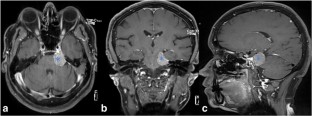

Fig. 3